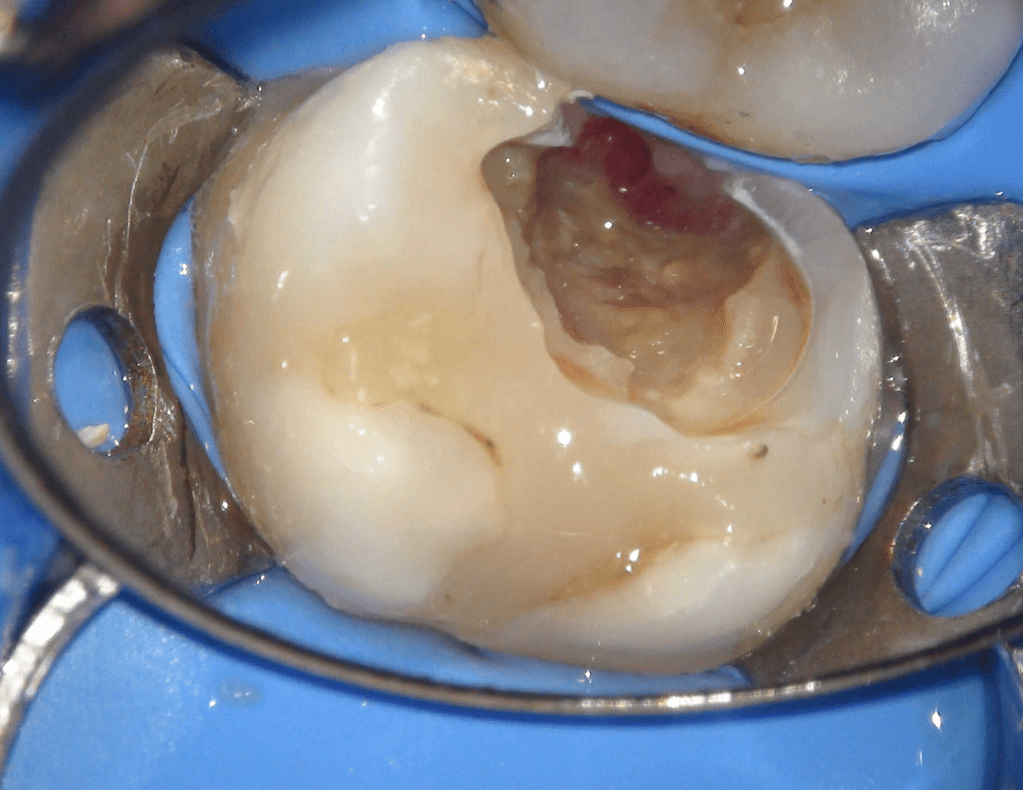

Reconstrucción preendodóntica

Reco pre-endo, molar inferior